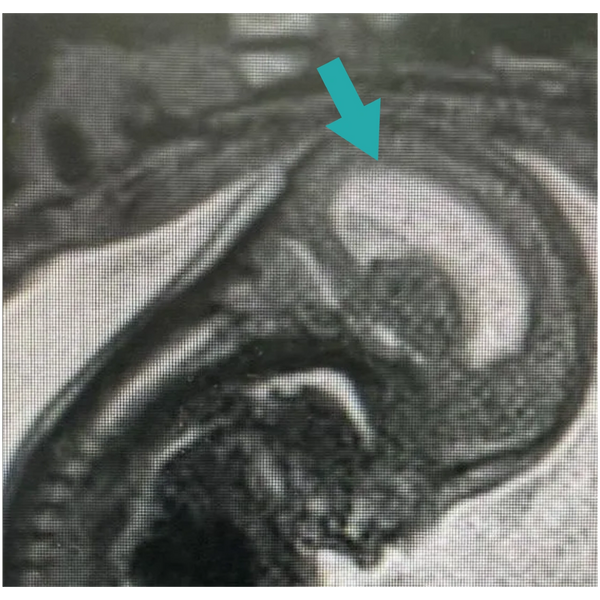

(Pic: MRI of a fetus with hydrocephalus, with the arrow demonstrating an enlarged lateral ventricle)

Hydrocephalus is often first suspected during routine prenatal ultrasound when enlarged ventricles (ventriculomegaly) are identified. When present, further evaluation is recommended to better understand the cause and guide care.